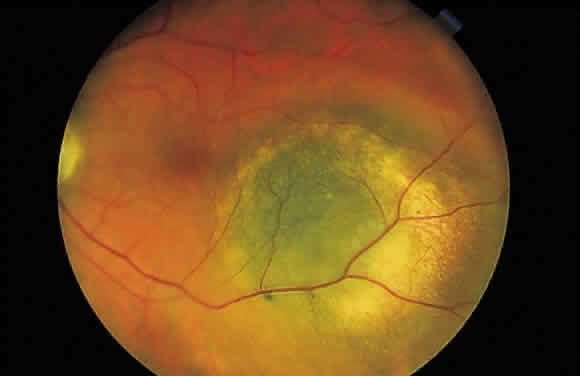

beneath the retinal pigment epithelium seems much darker. A hemorrhage in the nerve fiber layer (Fig. 11A) dissects along the plane of the layer parallel to the orientation of

the internal limiting membrane (see Fig. 11B). A hemorrhage located between the retinal pigment epithelium and Bruch's

membrane also spreads in a plane parallel to the orientation

of the membrane (Fig. 12). However, its extent is limited by the adhesion of the pigment epithelium

to Bruch's membrane, in contrast to a nerve fiber layer hemorrhage, where

no such delineating structure is present. Therefore, a fresh

nerve fiber layer hemorrhage appears bright red and has feathery

borders, whereas a subpigment epithelial hemorrhage appears brown-black

and has sharp borders (Fig. 13).  Fig. 11. A. Section of retina with hemorrhage in the nerve fiber layer (between the two large arrows). Notice that the limits of the hemorrhage are not clearly defined, since

posterior hyaloid is marked by four small arrows. B. Fundus photograph of nerve fiber layer hemorrhage. They are oriented parallel

to the plane of the internal limiting membrane. Because of their

dispersal within the ganglion cell layer, the borders are “feathery” (flame

shaped). Fig. 11. A. Section of retina with hemorrhage in the nerve fiber layer (between the two large arrows). Notice that the limits of the hemorrhage are not clearly defined, since

in the region of the ciliary body.  Fig. 16. Fundus photograph of a disciform macular scar, white because of fibrosis

and atrophy of the pigment epithelium. A broad, C-shaped, fresh hemorrhage

within the sensory retina surrounds it. Fig. 16. Fundus photograph of a disciform macular scar, white because of fibrosis

and atrophy of the pigment epithelium. A broad, C-shaped, fresh hemorrhage

within the sensory retina surrounds it.